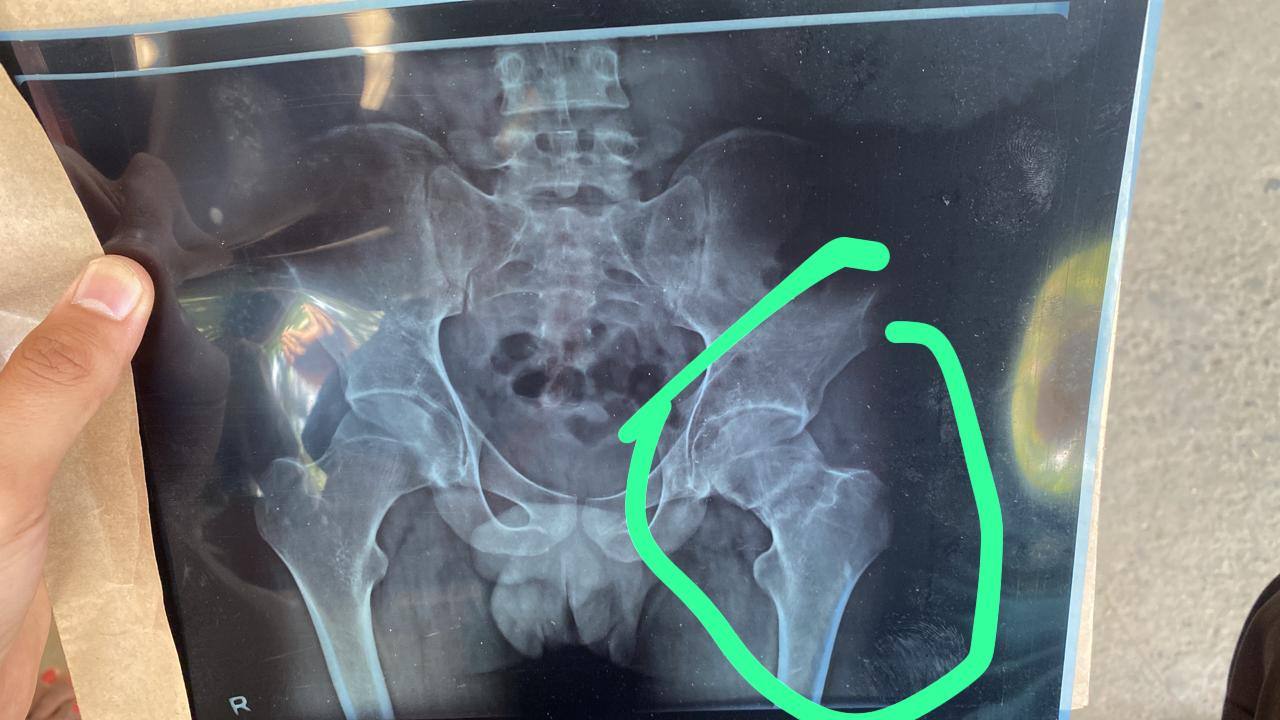

Sir main jab baithta hu aur jab Jada chalta hu ya pith ke bal sota hu to mere spinal cord me Jada dard hota Jada der v  baitha nahi jata h or jab pet ke bal sota hu to relax mehsus hota h isliye ap plzz meri report dekhkar bataye ki mujhe kya problem h

Sir please ek baar ye bta do ye fracture kitne tym mei theek ho jaata h